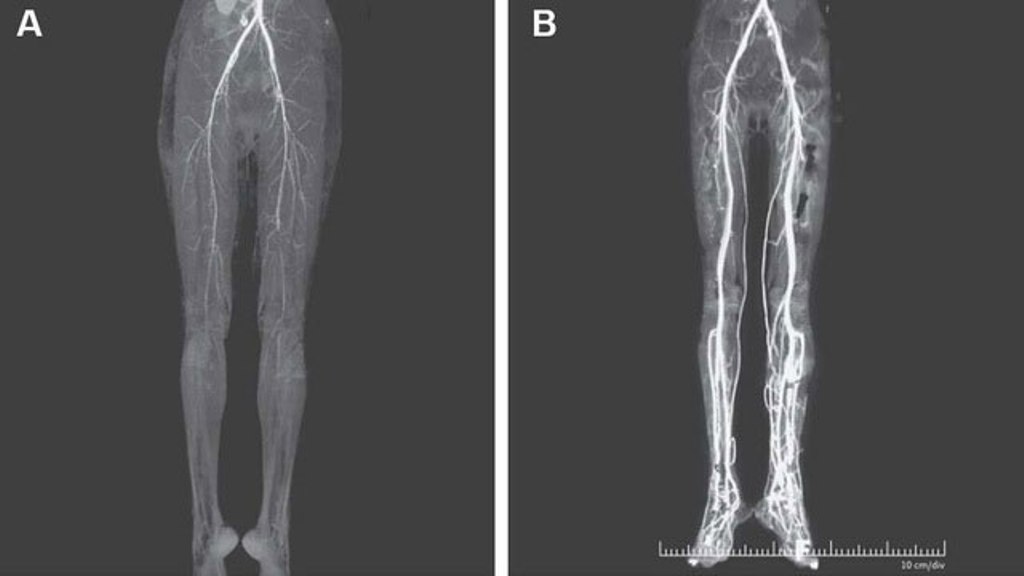

Hình ảnh chân bệnh nhân nữ trước và sau khi được truyền chất làm loãng máu.

Kết quả chụp cắt lớp vi tính (CT) cho thấy có dấu hiệu hẹp động mạch, sau đó cô được truyền chất làm loãng máu - heparin. Cơn đau ở chân được cải thiện và chân cô gái đã ấm hơn khi lưu lượng máu tăng lên. Tuy nhiên thật không may, một trong những ngón chân của cô đã phải cắt bỏ do hoại thư.

Hiện tại, hai tuần sau khi điều trị và ngừng dùng thuốc, lưu lượng máu ở chân cô gái đã được cải thiện và có tiến triển tốt.